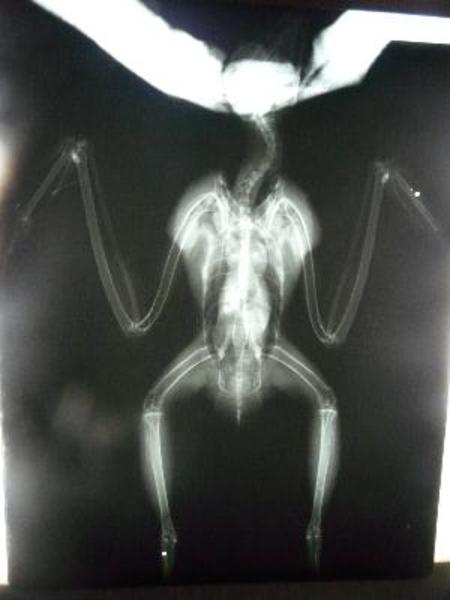

Se trata de Frodo, bautizado por Susana nuestra fisio, que ingresó en Grefa disparado.